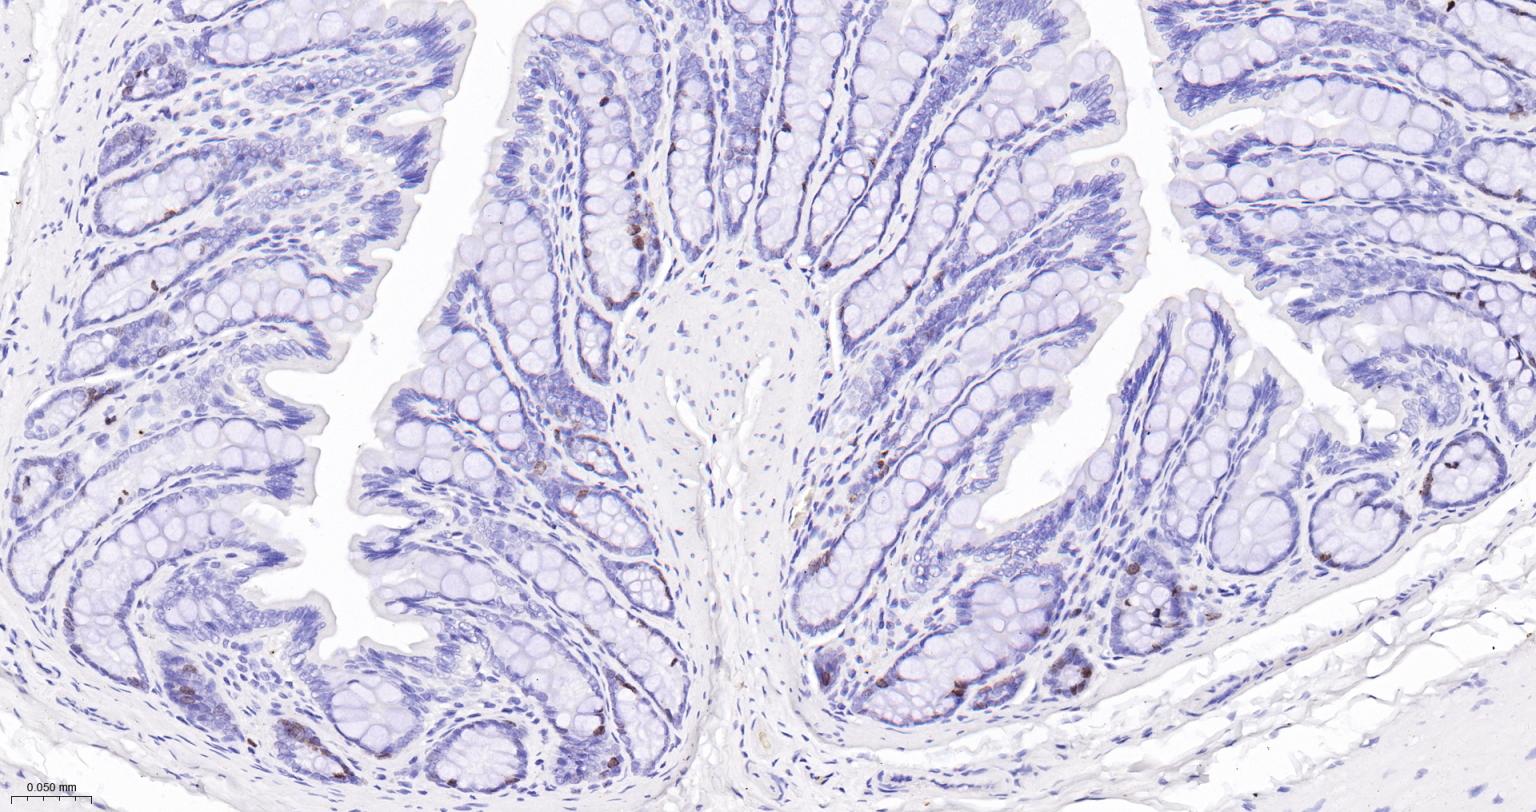

Paraformaldehyde-fixed, paraffin embedded Human Colon; Antigen retrieval by boiling in sodium citrate buffer (pH6.0) for 15 min; Antibody incubation with Ki67Monoclonal Antibody, Unconjugated(bsm-52455R) at 1:200 overnight at 4°C, followed by conjugation to the SP Kit (Rabbit, SP-0023) and DAB (C-0010) staining.